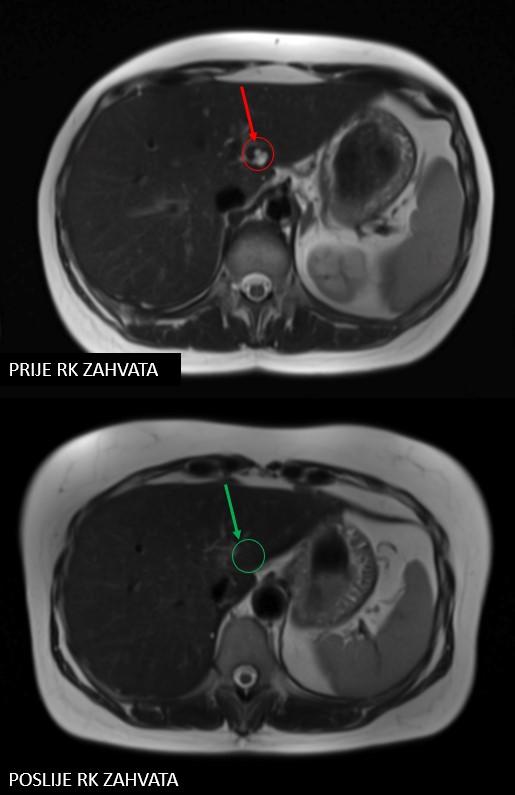

Rezultat – 47 mjeseci nakon RK

potpuni nestanak tretiranih lezija